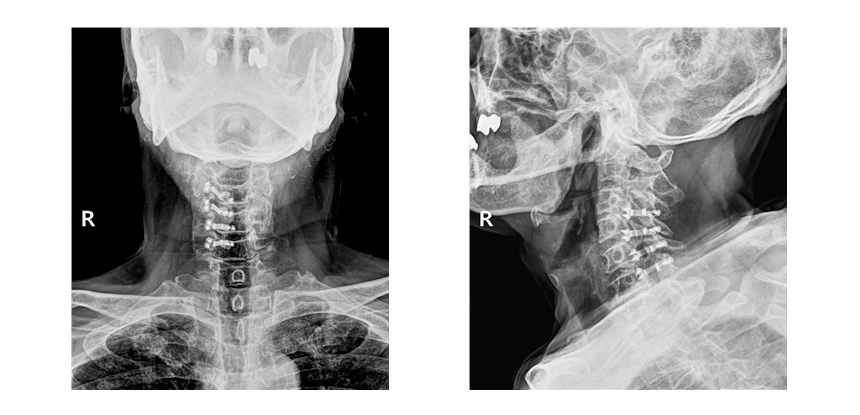

● 진단 요추관협착증 진단하기 위해서는 문진과 보행시 얼마나 걸으면 아픈지 파악하여 일상생활의 불편감이나 통증의 특징을 알아보고 근전도검사와 CT 및 MRI를 촬영하여 통하여 진단합니다. ● 치료 보존적인 치료는 약물치료, 물리치료를 시행하고 증상이 지속적으로 나타나는 경우에는 수술적치료인 후궁절체술 및 후궁성형술을 시행하여야 합니다. 후궁성형술을 시행한 사진 ![]() |